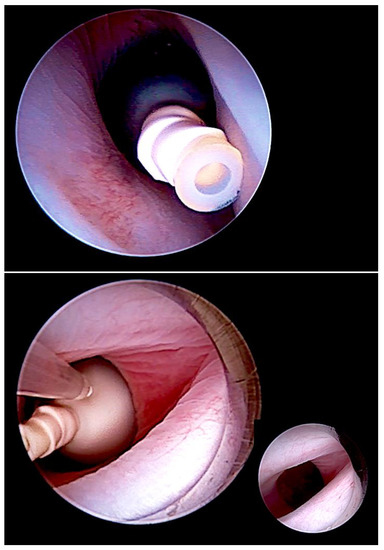

Figure 2.

Minimally invasive, fully percutaneous fetoscopic tracheal balloon occlusion (FETO) (top) for the treatment of fetuses with severe pulmonary hypoplasia. FETO has most commonly been used in fetuses with diaphragmatic hernia. In addition, we observed it to be also particularly effective for the treatment of lungs compromised by long-standing anhydramnios following early preterm premature rupture of membranes prior to 20 weeks of gestation. It can also be applied to save fetuses with pulmonary hypoplasia from poorly distending and poorly perfused lungs after drainage of severe hydrothorax or after volume reduction of CPAMS. Following a period of one to several weeks, the balloon is removed by a second intervention (bottom).